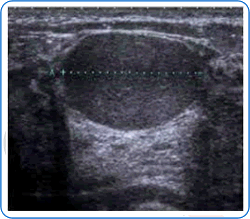

Ultrasound

Ultrasound machines use sound waves to image various areas of the body, including the breasts.

The sound waves are transmitted through a probe, which is placed directly over the breast. Lubricating gel is placed on the breast skin to improve contact. The sound waves are reflected within the breast back to the ultrasound machine, which transforms them into a computer image viewed on a display monitor.

The ultrasound examination is carried out by the Consultant Breast Radiologist, who decides whether any abnormalities are present. The test is very good at differentiating between solid lumps and fluid-filled lumps (cysts). It is particularly useful in women under the age of 40, since younger breasts are much denser; this means that abnormalities may be sometimes difficult to visualise on mammograms in this age-group. Ultrasound examination does not usually cause any pain.